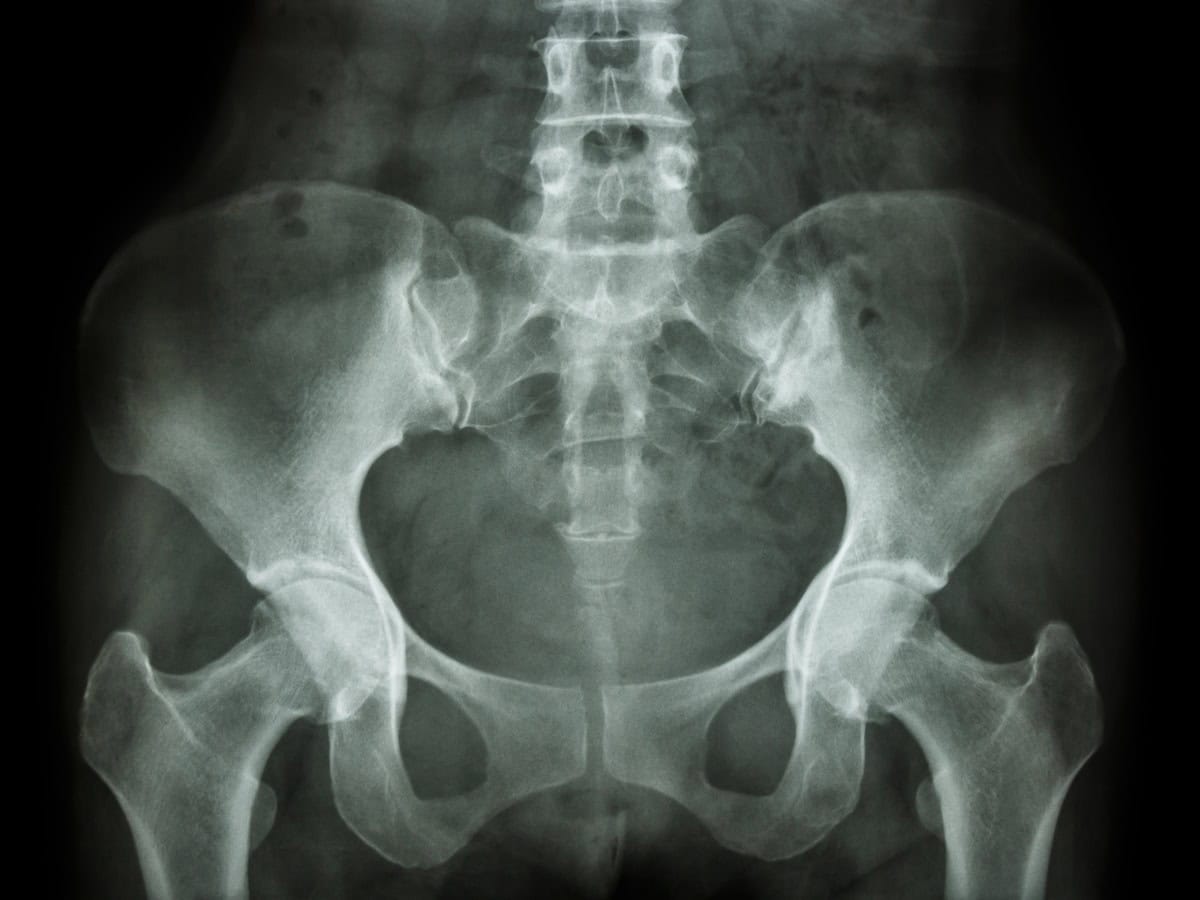

Men have a pelvic floor too. This group of muscles sits at the base of the pelvis and plays a critical role in bladder and bowel control, sexual function, and core stability. When the pelvic floor muscles are not working correctly, whether weakened, overactive, or poorly coordinated, a range of uncomfortable and often distressing symptoms can result.

Men’s pelvic health physiotherapy involves a detailed assessment of the pelvic floor muscles and surrounding structures, followed by a personalised treatment programme to restore normal function, reduce pain, and improve quality of life. Our specialist physiotherapists in Sutton are experienced in assessing and treating the full spectrum of male pelvic health conditions.